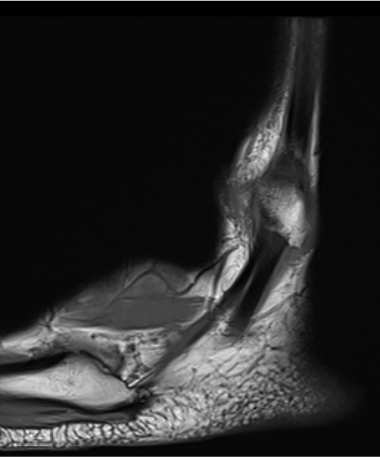

MRI

Anterior subluxation of peroneal tendons

Anterior subluxation of peroneal tendons